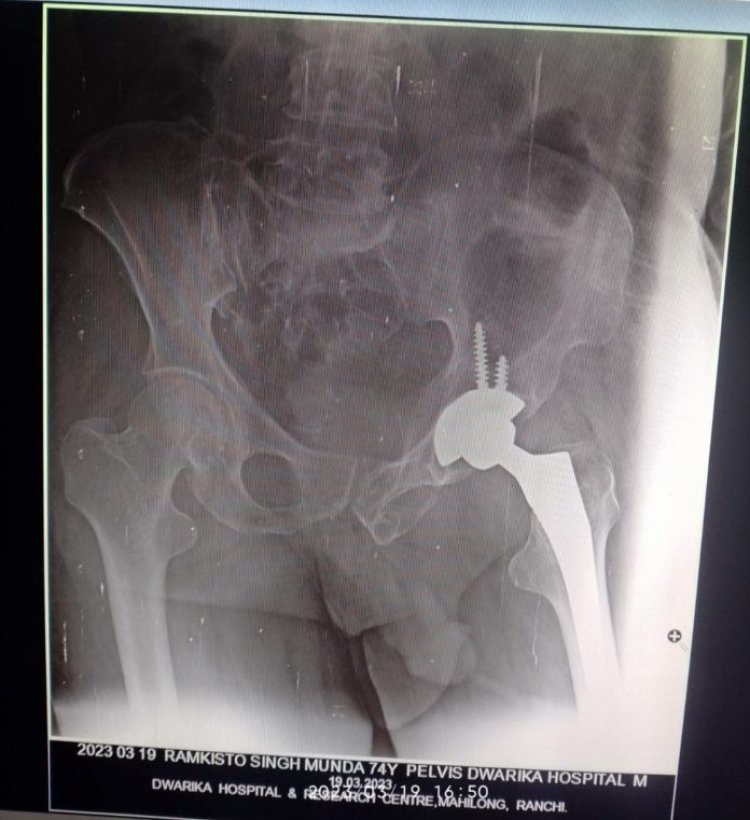

करीब एक साल पहले राम किष्टो सिंह मुंडा का कुल्हा (कमर के नीचे और जाँघ के ऊपर का जोड़) टूट गया था। जिसके कारण वे असह्य दर्द से परेशान रहते थे। इसकी वजह से उन्हें रोजाना के कामों को करने में काफी दिक्कत होती थी। राम किष्टो सिंह मुंडा की उम्र करीब 75 साल है। उनको दर्द इतना बढ़ गया था कि वह अपने पैरों पर खड़े भी नहीं हो पा रहे थे। इस परेशानी को लेकर वे शहर के अन्य चिकित्सकों से भी मिले लेकिन अत्यधिक खर्च जानकर पैसों के अभाव के कारण वो अपना समुचित इलाज भी नहीं करवा पा रहे थे। अंत में राम किष्टो सिंह मुंडा अपने ग्राम मुखिया से मिले। उनकी इस दशा को देखते हुए उनके ग्राम के मुखिया ने तय किया वह राम किष्टो सिंह मुंडा का इलाज द्वारिका अस्पताल में आयुष्मान भारत योजना के तहत बिलकुल मुफ्त में करवाएंगे । इसके मुखिया ने द्वारिका अस्पताल से संपर्क किया। जिसके बाद अस्पताल के चिकित्सकों की टीम ने बिना देरी किये राम किष्टो सिंह मुंडा की रिपोर्ट्स मंगवाई और उनकी स्वास्थ्य स्थिति को देखते हुए अस्पताल ने उनको टोटल हिप रिप्लेसमेंट कराने की सलाह दी।

फिर आयुष्मान भारत योजना के तहत द्वारिका अस्पताल की टीम के द्वारा राम किष्टो सिंह मुंडा का इलाज किया गया । इलाज के बाद अब राम किष्टो सिंह मुंडा बिलकुल स्वस्थ महसूस कर रहे हैं। द्वारिका अस्पताल के डॉक्टर्स के द्वारा उन्हें अस्पताल से डिस्चार्ज कर दिया गया है।